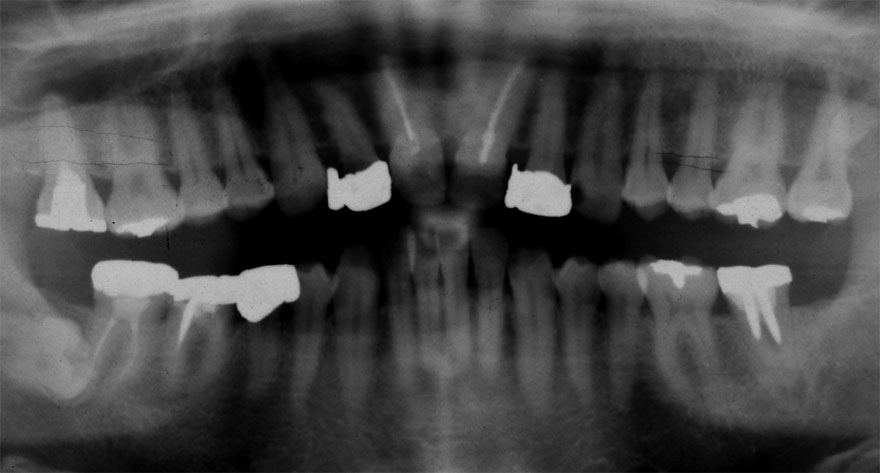

初診時 36歳 女性 平均歯槽骨喪失量:2.70mm

30年後 66歳

平均歯槽骨喪失量:3.26mm

30年間喪失量:-0.55mm

年間喪失速度:-0.018mm

(ケア頻度:3.01ヵ月ごと)